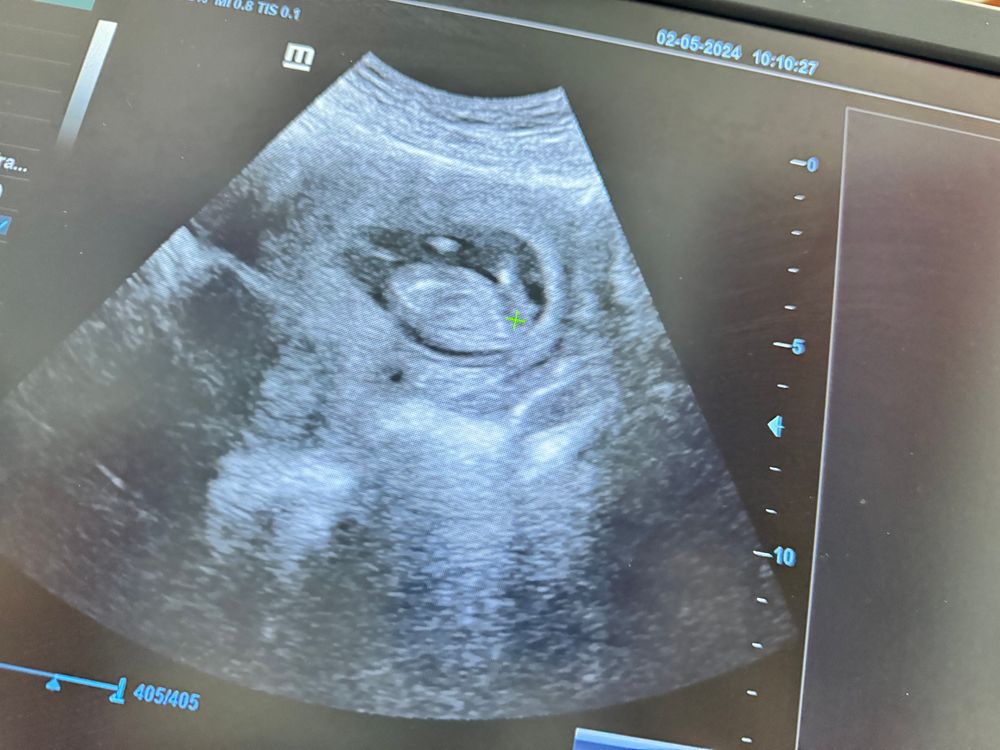

УЗИ в 13 недель

по этому фото непонятно, если честно 😅

Анна, напротив плюсика видите белое как точечка

Саяна , тут сложно сказать. Обычно я сразу вижу по бугорку, но это когда малыша полностью видно 😄

Ребеночек 😂 Так сложно очень определить , даже врачу узисту на таком сроке Недель в 15 смогут сказать

Елизавета , тут многие по бугорку отпределяли поэтому решила посмотреть а вдруг и мне смогут